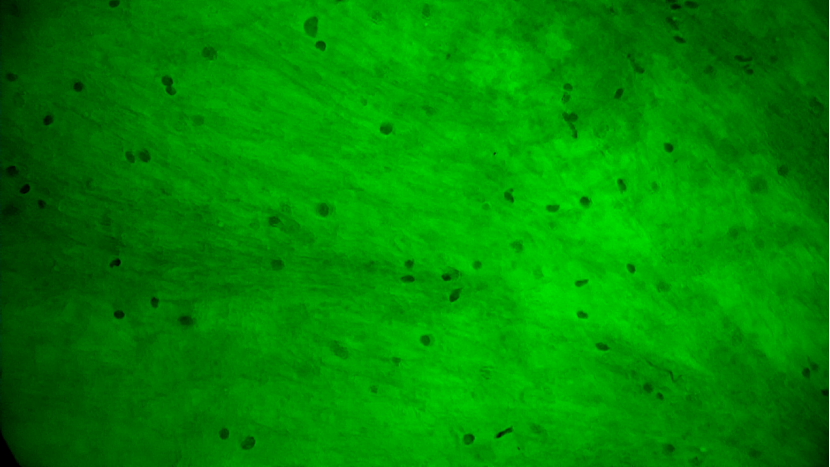

手術(shù)切緣處發(fā)現(xiàn)的正常腦白質(zhì):細胞核形態(tài)正常,密度低且分布均勻